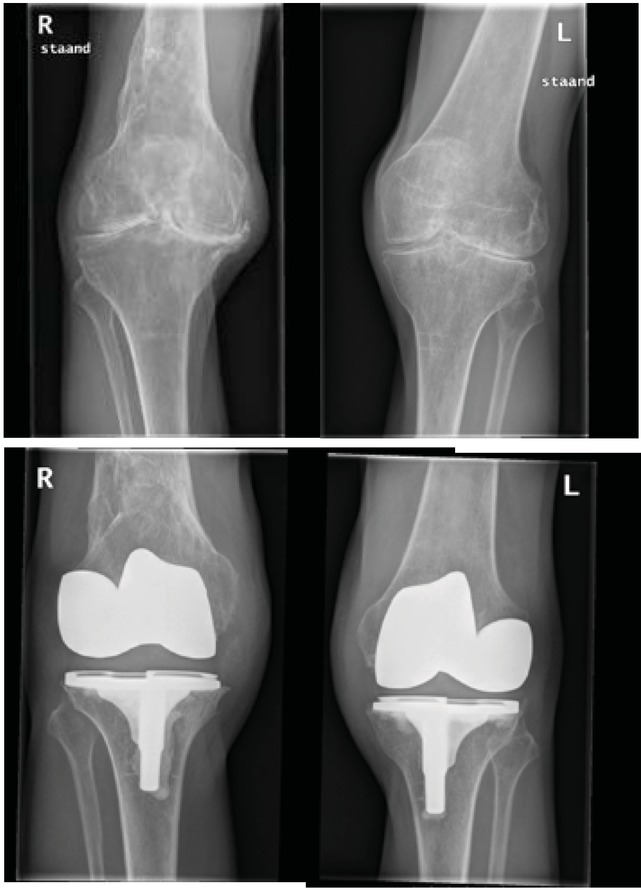

Case 3 – Bilateral TKA

This patient is a married man with three children and four grandchildren. He is unemployed but active in upholstering on a voluntary basis. In 1995, he has a THA left side.

He recieved rehabilitation In hospital: AROM was regained by active exercise (assisted in the first week) with passive exercise by means of a continuous passive machine (CPM). He was discharged eight days post-surgery. At home, he used two crutches during the first 2 months. He received daily physiotherapy sessions for 1 year, and hydrotherapy (UMC Utrecht) twice-weekly, although this was stopped after a few months. There was very little progression in standing and walking.

Surgery was postponed by the patient himself for too long. Unfortunately, he is unable to ride a bicycle, although he is physically much more active and has more energy: he is very pleased to be able to do activities with his grandchildren.

Post-operative pain assessment scores on the VAS (0–10) was on average 0.3 (range 0–1), indicating minimal pain in all cases. Retrospectively pain improved of all the joints operated on: Case 1: LK 3 and 1 (△= 2) and RK 3 and 1 (△= 3); Case 2: LA 2 and 0 (△=2) RA 2 and 0 (△=2); Case 3: LK 3 and 0 (△=3) and RK 3 and 0 (△=3). The active range of motion of four knees (cases 2 and 3) increased between 5 and 10 degrees, and extension 0 till 20 degrees. As a result of the fixation of the tibiotalar joint, active range of motion decreased in case 1; plantar flexion average 15˚ (range 10– 20˚) and dorsiflexion average 7.5˚ (range 5–10˚).

Self-reported basic lower activities on the HAL showed an improvement (range 20–46.5) in all patients. The scale of this effect over one standard deviation (of 18)[9], i.e. with an effect size of >1, is generally considered to be large [10]. The increase in the score for complex lower activities was less pronounced (range 3.5–40); no data on standard deviations were available for this summary score. The difference of the lower complex activities was evident: cases 2 and 3 increased (figures 2 and 3), whereas case 1 showed an increase. The MACTAR priority lists confirm improved activity levels in each patient - shown in tables 2, 3 and 4 - but individual differences are clearly visible.